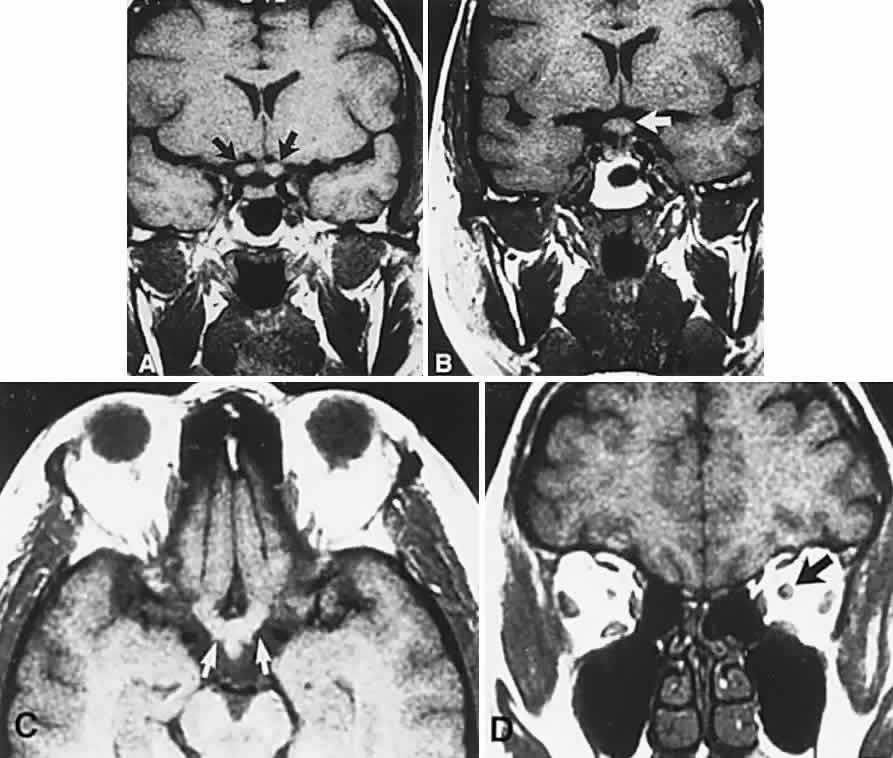

Fig. 3. Neuroimaging of pituitary adenomas. A. Axial computed tomography (CT) section shows a round tumor mass filling the suprasellar cistern; ring enhancement (arrows) indicates subcapsular hemorrhage. B. Contrast-enhanced coronal CT section through a large invasive adenoma. Note encasement of the carotid artery (arrows) and the position of the middle cerebral artery above (arrowheads). C. Axial CT section shows lateral expansion into the cavernous sinuses (white arrows) and a necrotic cyst (black arrow). D. Subfrontal superior extent of the mass. Note the middle cerebral arteries. E. Magnetic resonance imaging of a large lobulated prolactinoma, with suprasellar extension. Note the distortion of the third ventricle (open arrows) and extension toward the temporal lobe (long arrow); the tumor has not involved the sphenoidal sinus (s). F. Chiasm (arrowheads) is draped on the superior surface of the tumor (TR, 550 milliseconds; TE, 26 milliseconds). G. Sagittal section shows suprasellar growth with the chiasm above (arrowheads); the sella (arrows) and sphenoidal sinus (s) are normal (TR, 850 milliseconds; TE, 26 milliseconds). H. Hyperintense signal (TR, 2000 milliseconds; TE, 60 milliseconds) indicates the partial cystic character. Sagittal (I) and axial (J) sections with head tilt to the right, in case of a large cystic adenoma with an interface level between newer blood (white arrow) and older blood (black arrow) (TR, 800 milliseconds; TE, 30 milliseconds). K. Signal difference is intensified (TR, 2100 milliseconds; TE, 80 milliseconds). L. Hemorrhage (bright signal, arrow) in a pituitary adenoma with headache and bitemporal field depressions. M. Without interventions, 2-month follow-up showed spontaneous involution, with normal pituitary gland (arrow), stalk, and chiasm.

Clinical signs and symptoms include the following: acute onset of severe headache, often sickening frontal or retro-bulbar cephalgia, or other less disabling change in headache pattern; acute or rapidly progressing unilateral or bilateral (usually asymmetric) ophthalmoplegia due to rapid expansion into cavernous sinuses (see also Volume 2, Chapter 12); epistaxis or CSF rhinorrhea when the mass ruptures or erodes into the sphenoid sinus; complications of blood or necrosis debris in the CSF, with “pseudomeningitis”; rapid neurologic deterioration and obtundation, although patients need not be stuporous; and, greater or lesser degrees of hypopituitarism.62,63 Selective expansion laterally into the cavernous sinus may produce ophthalmoplegia without visual loss; selective expansion superiorly may produce visual loss without ophthalmoplegia. Almost without exception, enlargement of the sella is found even on plain skull film views; both CT and MRI detect fresh hemorrhage (Fig. 3), but MRI may fail to demonstrate acute hemorrhage unless specific sequences are employed (hemorrhage may be isointense on T1-weighted images and hypointense on T2-weighted images; in the subacute phase, extracellular methemoglobin should appear bright on both T1 and T2 sequences). Corticosteroid replacement and other supportive measures may be critical, and, in most instances, decompression through the sphenoid sinus is advisable, sooner rather than later. Bromocriptine has been suggested as a temporizing measure when signs and symptoms are modest and not progressing,64 and there are advocates65 for conservative management consisting of intravenous dexamethasone, so long as visual deficits are minimal or rapidly improve; otherwise decompressive surgery is required. Given the regularity with which pituitary apoplexy is often a delayed diagnosis, being confused with ruptured aneurysm or meningitis, for example, and that transsphenoidal surgery is a relatively simple undertaking, further procrastination in decompression of the compromised visual pathways is to be avoided.